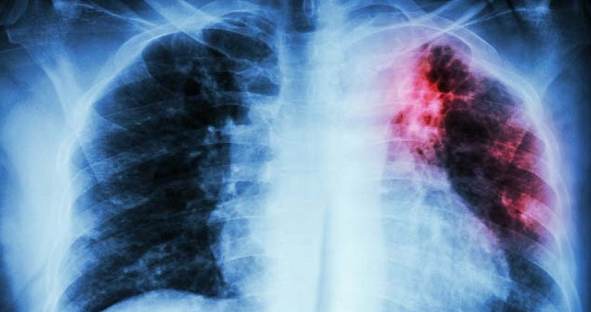

Vi khuẩn lao còn có tên là Mycobacterium tuberculosis. Vi khuẩn này có thể gây ra nhiều loại lao khác nhau nhưng lao phổi là phổ biến nhất. Bạn có thể bị nhiễm vi khuẩn lao nếu bạn hít phải giọt nhỏ dịch tiết đường hô hấp của người bị lao. Mặc dù lao có thể phòng ngừa và điều trị được nhưng theo Tổ chức Y tế Thế giới, có khoảng 66% người bị lao sẽ tử vong nếu không được chăm sóc y tế thích hợp.

Bạn nên đến gặp bác sĩ ngay lập tức nếu bạn có triệu chứng của bệnh lao. Bác sĩ sẽ tiến hành hỏi bệnh, thăm khám lâm sàng và có thể chụp Xquang phổi. Nếu bạn nghĩ mình có thể bị lao hoặc từng tiếp xúc với người mắc bệnh thì bạn cần làm một số xét nghiệm.

Bệnh lao không được điều trị thường gây tử vong. Mặc dù được điều trị nhưng lao vẫn có thể gây ra những tổn thương vĩnh viễn ở phổi, khiến bạn bị khó thở hoặc suy hô hấp.

Lao phổi không điều trị có thể lan truyền sang các cơ quan khác, ví dụ như não, gan hoặc tim. Nó có thể gây tổn thương những cơ quan này và dẫn đến tử vong.